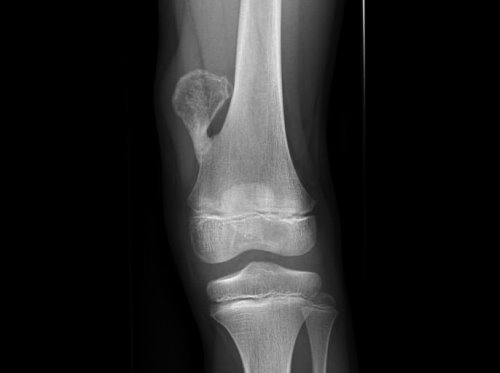

Обнаружить экзостоз можно на рентгеновском снимке, или при пальпации, которую приводит врач на осмотре.

По форме образование может иметь быть грибовидным, шиповидным, как цветная капуста.

В коленном суставе экзостома растет рядом с концом бедренной трубчатой кости или внутри сустава.